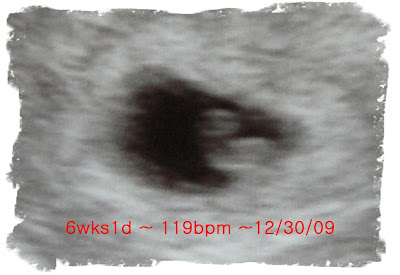

This is my last son at 6 weeks. There is a heart beat

7 weeks

8 weeks

9 weeks

10 weeks

11 weeks